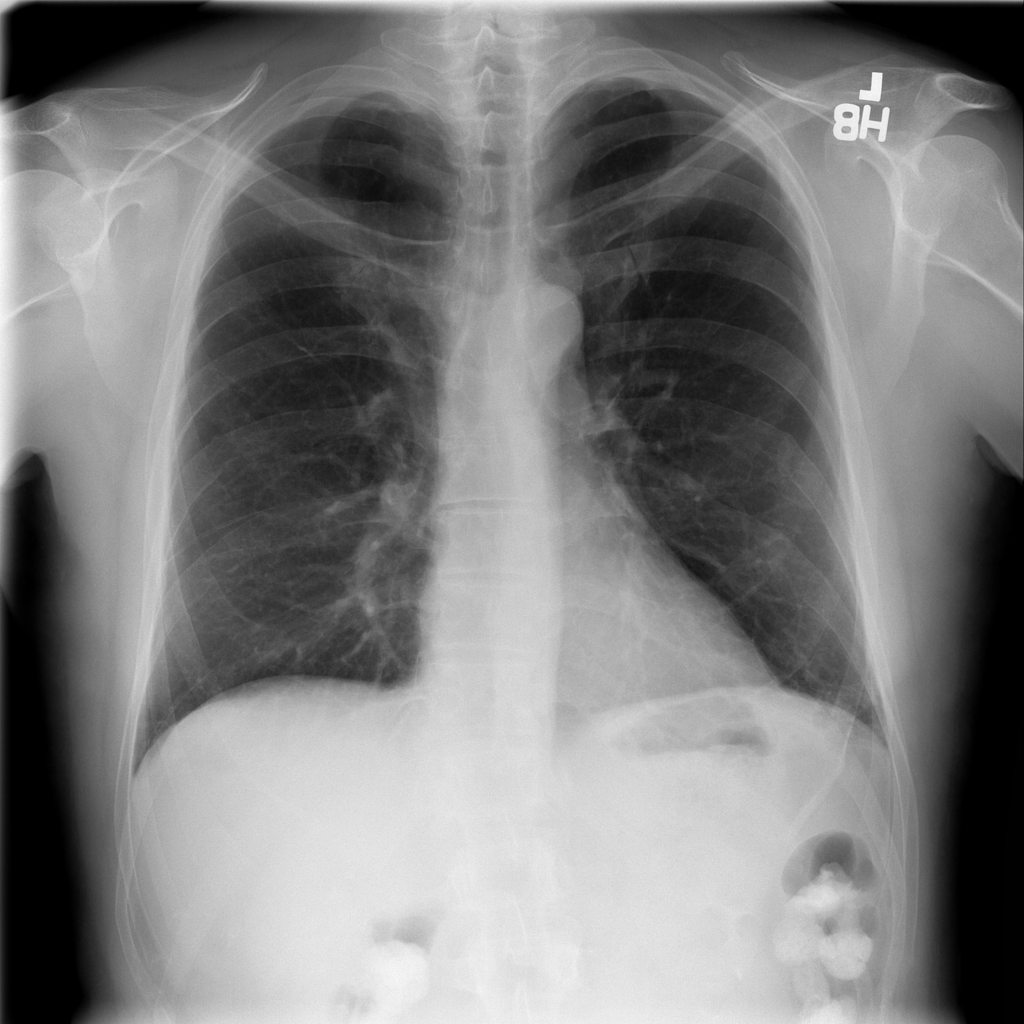

PAT-C77C · IMG-003Fibrosis

PAT-C77C · IMG-003

PA